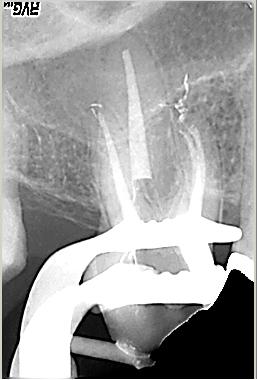

Zustand unmittelbar vor Behandlungsbeginn im Juni 2003. Die Fraktur des distalen Zahnanteils hat die Patientin jetzt zur Einwilligung in die Behandlung motiviert. Auffällig ist in dieser Projektion die besonders starke Krümmung der mb Wurzel sowie die knochennahe Defektlage distal. Es erfolgte zunächst die Kariesentfernung gefolgt von einer chirurgischen Kronenverlängerung zur Herstellung der biologischen Breite sowie Ermöglichung des sog. Ferrule-Effektes. Danach wurde der Zahn adhäsiv aufgebaut. Erst jetzt wurde mit der eigentlichen WKB begonnen

Röntgenmeßaufnahme

Röntgenmeßaufnahme nach vorgängig durchgeführter endometrischer Längenbestimmung